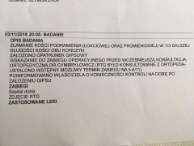

potwierdzenie weterynarza cz. 2